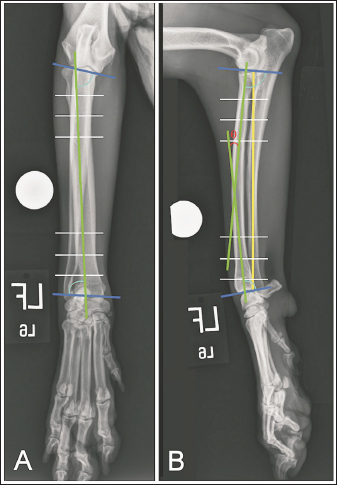

Mixed breed dogs euthanized for reasons unassociated with the study were obtained. All cadavers had been previously frozen but were thawed and stored in a cooler for a minimum of 3 days prior to use. Bilateral orthogonal radiographs were obtained (Vet-ray, Sedecal, Niles, IL) of the antebrachium and manus to ensure normalcy and allow for preemptive measurements of antebrachial morphology. A 25-mm diameter sphere was placed adjacent to the radius in all images to allow for image calibration. Image analysis was performed on a dedicated computer using DICOM viewing software (MergePACS, Merative, Ann Arbor, MI). Angle measurements were made using a Chrome browser protractor extension (“Protractor”, Ben Burlingham) and lengths were calculated in an orthopedic planning program (vPOP PRO, VETSOS Education Ltd., Ojai, CA). Joint reference lines, anatomic axes, radial joint angles, and frontal and sagittal plane alignments were established as described by Fox and Tomlinson (2018). Procurvatum was quantified as the acute angle (theta) created from the intersection of the proximal and distal radial sagittal anatomic axes. The radial length was measured on sagittal view images and defined as the distance between the caudal margins of the radial head and of the distal radial articular surface (Fig. 1).

Fig. 1. Orthogonal radiographic images illustrating how joint reference lines (dark blue) and anatomic axes (green) were established to define the proximal and distal anatomic radial joint angles (light blue) on intact limbs. White lines are paired with 10% (outermost lines), 20% (middle lines), and 30% (innermost lines) markers along the length of the proximal and distal radius used to define anatomic axes. Radial length (yellow) was measured as the distance between the caudal margins of the articular surface of the radial head and of the distal radial articular surface. Theta (θ) was measured as the acute angle created at the intersection of anatomic axes.